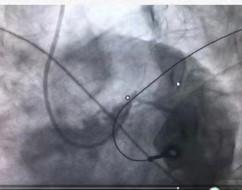

周亚峰副院长和张强主任接到消息,判断病人情况危重,急需手术治疗,立即至导管室进行各项术前准备,严阵以待。然而,刚抵达导管室门口沈先生就突发室速室颤、意识丧失、抽搐和呼吸停顿,随行医务人员立刻就地抢救,边进行心肺复苏边将沈先生转移至手术台上。手术过程中沈先生仍有室速室颤反复发作的情况,共进行8次紧急电除颤(见图1),术中导丝通过冠脉导管迅速送至冠脉血管,发现前降支近主干段完全闭塞(见图2),回旋支开口至近段狭窄50%,右冠开口狭窄约80%,周亚峰副院长以最快速度开通“罪犯血管”,于前降支近段植入支架一枚(见图34)。经过一个多小时的抢救和手术,患者胸痛症状明显减轻,手术取得圆满成功。

图2 前降支近主干段完全闭塞           图3 前降支近段植入支架一枚,开通血管